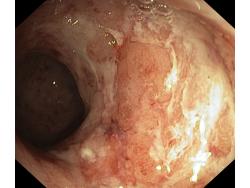

Zapalenie wrzodziejące...

Zapalenie wrzodziejące jelita grubego